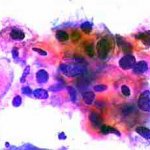

Δυσπλασίες τραχήλου μήτρας σοβαρού βαθμού (CIN III)

Ασυμπτωματική ασθενής 39 ετών. PH κόλπου 4,4. Κολποσκόπιση:

Στην δοκιμασία οξικού οξέως και στην δοκιμασία Lugol, αρνητική περιοχή, τόσο στο πρόσθιο, όσο και στο οπίσθιο χείλος του τραχήλου, σε ακτίνα 3-4 χιλ. και πλάτος περίπου 5 χιλ., με εικόνα διακριτικού επίπεδου μωσαϊκού.